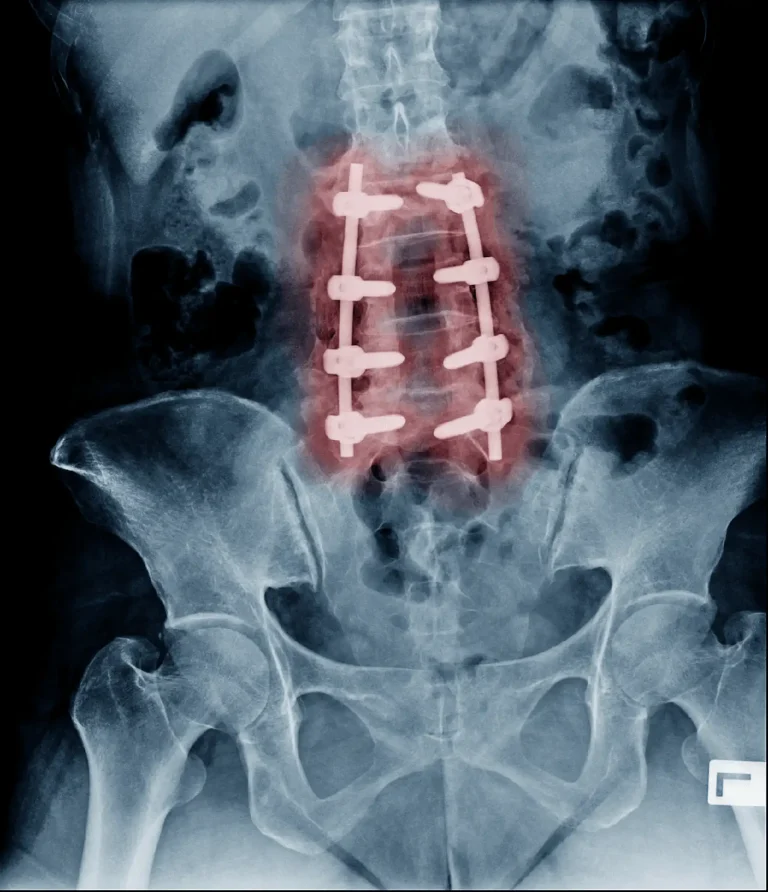

X-ray showing spinal fusion with screws and rods from front and side views.

Back Pain Gets Worse

Back pain becomes worse after laminectomy. Fusion will be recommended.

X-ray of a spine with red-highlighted spinal fusion hardware.

90%+ Need Additional Surgery

Additional surgery will be necessary in over 90% of patients having laminectomy.